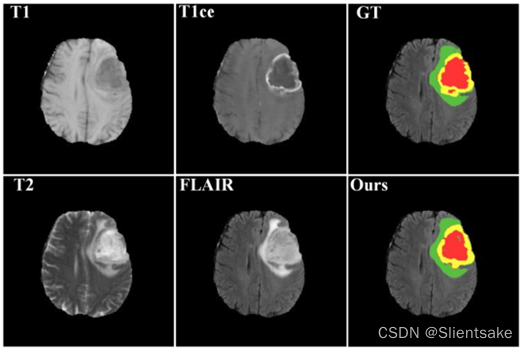

医学图像分割为医学专业人员实现疾病诊断、肿瘤生长监测、治疗规划和随访服务提供基础性指导和定量评价。图1显示了脑胶质瘤分割任务的概述。

图1:BraTS17多模态图像切片的例子与真实标签和网络的分割结果。在该图中,绿色代表增强肿瘤(数字标记2),黄色代表水肿(数字标记1),红色代表坏死和非增强Tumor Core (NCR\ECT,数字标记4)。